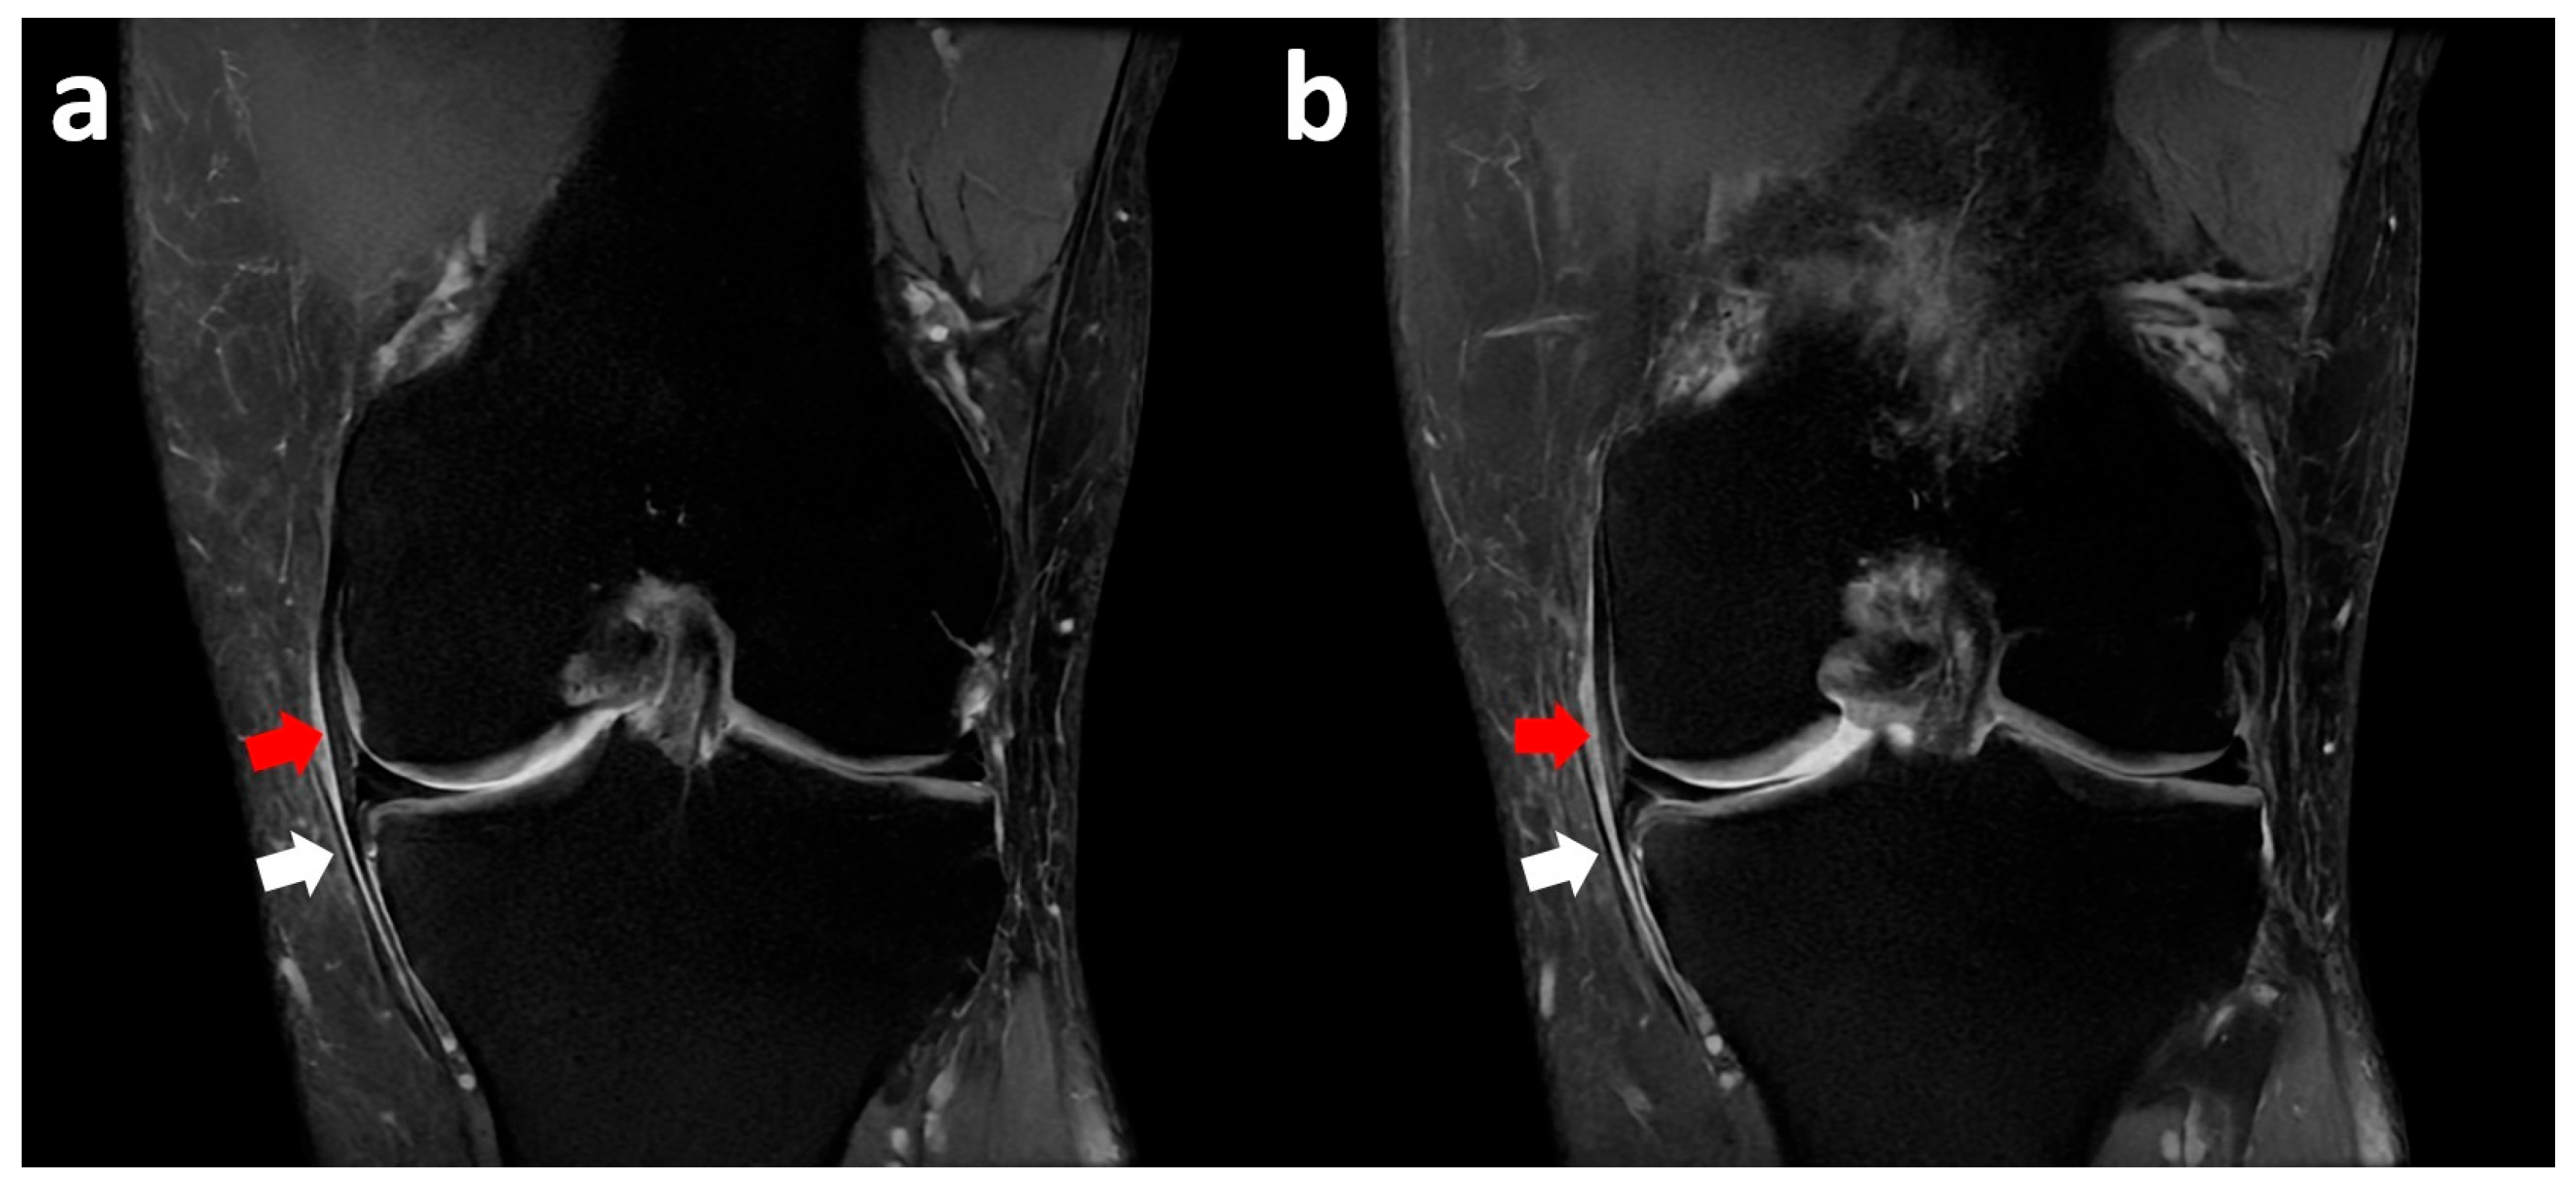

3.1. Medial Meniscus Flap Under the Medial Collateral Ligament

3.2. Medial Meniscus Radial Tear with Flipped Body